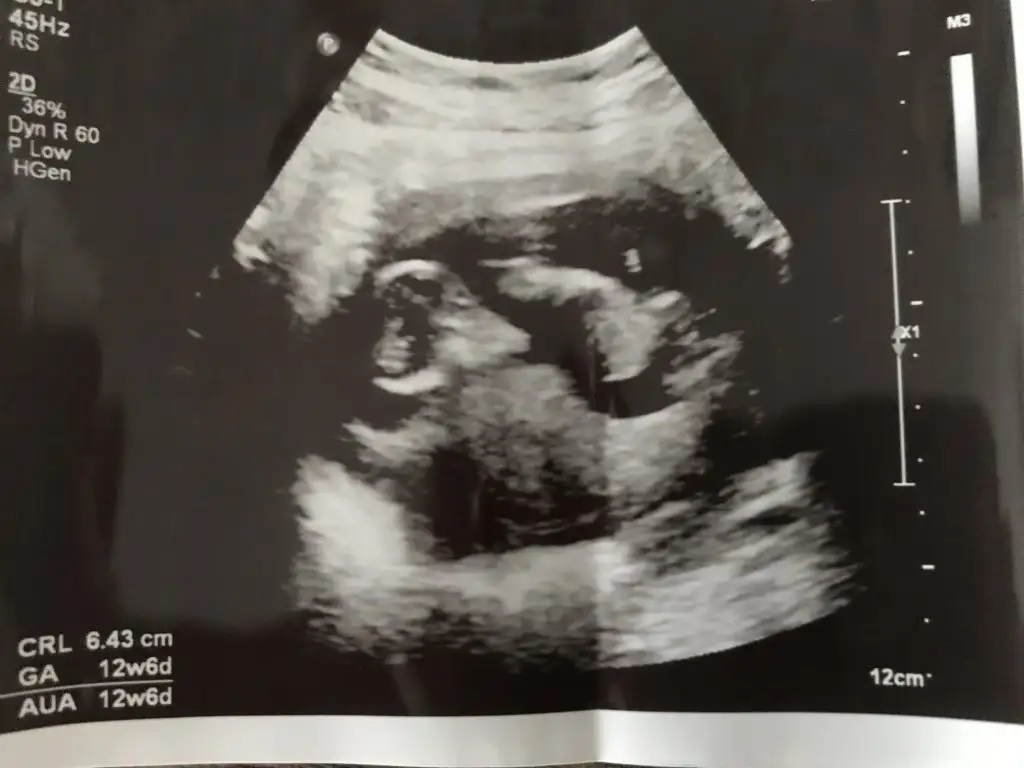

Sanki erkek gibiMerhaba 12+6 haftalık. Yorumlarmısınız acabaIkra meyra

Kız gibi sanki

TeşekkürlerSanki erkek gibi